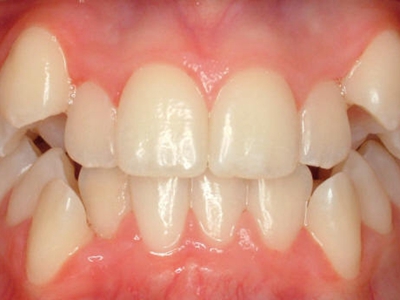

牙龈退缩牙龈轻度萎缩图

牙龈退缩患者的上排牙和下排牙多颗牙齿的牙龈发生回缩,从而造成牙根轻微暴露,患者会出现牙根面敏感、口臭等症状,需要牙周治疗或脱敏治疗。